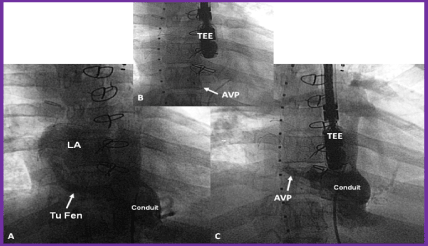

Cyanosis and cerebrovascular accidents: Fontan fenestrations created intentionally or residual defects between the lateral tunnel or extracardiac conduit and the atrial mass may cause right to left shunt because of higher Fontan conduit pressure than the atrial pressure. These residua not only produce arterial hypoxemia and cyanosis but also become sites for paradoxical embolism causing TIAs and CVAs and other systemic emboli. Transcatheter occlusion (Figure 8) of the fenestrations and atrial defects with conventional atrial septal closing devices should be performed. Test occlusion of the fenestration should be done to ensure that adequate cardiac output is maintained after closure. Some surgeons place tubular fenestrations and these may require coils, Amplatzer vascular plug (AGA Medical, Golden Valley, Minnesota) (Figure 9) or other devices. Late follow-up results after fenestration closure appear encouraging [81].

Figure 9. A. Selected cine frame from a Fontan conduit cineangiogram in antero-posterior view, demonstrating tubular fenestration (Tu Fen) with opacification of the left atrium (LA). B. The Tu Fen is closed with an Amplatzer Vascular Plug (AVP). C. A follow-up conduit cineangiogram after AVP implantation, showing complete occlusion of the Tu Fen. TEE, trans-esophageal probe. Reproduced from Rao PS. (2013) J Cardiovasc Dis Diagn 1: 104, 2013.